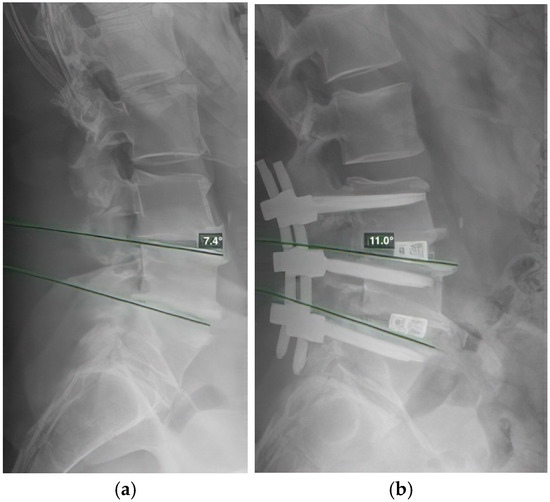

To verify the placement of the interbody cages, we used radiographic assessment to confirm that the cages were positioned in the anterior third of the intervertebral space. Angular measurements included segmental lordosis, defined as the angle between tangent lines and the superior endplates of two adjacent vertebrae (Figure 1), with each segment measured separately in multisegmental procedures; and lumbar lordosis, defined as the angle between the tangent lines and the superior endplates of L1 and S1. All radiographic measurements were conducted at the post-operative six-month follow-up to assess global and segmental lumbar lordosis outcomes.

Figure 1. Measurement of segmental lordosis, defined as the angle between the tangent lines and the superior endplates of two adjacent vertebrae. (a): Lateral radiograph of the lumbar spine showing preoperative segmental lordosis and the measured segmental lordosis. (b): Lateral radiograph of the lumbar spine 6 months postoperatively, following spondylodesis of L3–L5 with 10° TLIF cages, showing the measured segmental lordosis of the L4–L5 segment.